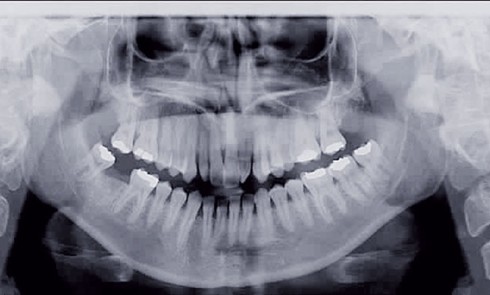

Nous sommes en présence d’une patiente adolescente âgée de 12 ans ½ dans une phase de croissance faciale favorable.Elle présente...

ODF